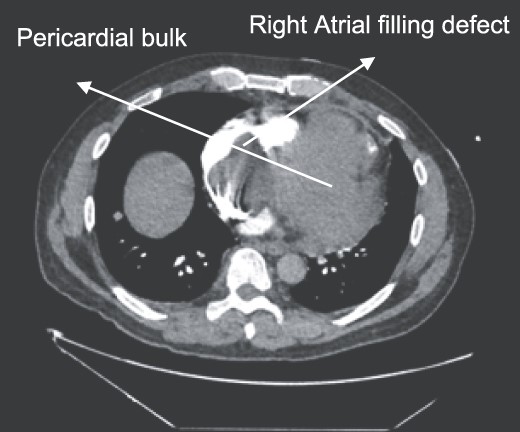

A 52-year-old gentleman was admitted to a district general hospital for shortness of breath causing type 1 respiratory failure with oxygen saturations of <90% despite high flow oxygen. His past medical history was unremarkable, and he was usually fit and well. A CT Pulmonary Angiogram (CTPA) was undertaken, which showed a heterogeneous oval-shaped lesion measuring 15 × 9 × 14 cm3 between the heart and the diaphragm, with a median attenuation of 35 HU and no enhancement during the arterial phase. Further solid lesions of 14 mm in the right lower lobe and 5 mm in the right upper lobe raised the suspicion of a primary cardiac sarcoma with pulmonary metastasis. This is shown in Fig. 1. Subsequent urgent CT staging (Fig. 2) was undertaken, which confirmed an indeterminate space occupying the inferior pericardial space, right atrial (RA) filling defect and anterior nodular pericardial thickening. No intra-abdominal or bone lesions were identified. An echocardiogram also confirmed these finding with the addition of no flow through the tricuspid valve (TV), as shown in Fig. 3.

CTPA showing oval-shaped heterogenous lesion as well as RA filling defect.

CT thorax-abdomen pelvis, depicting the RA filling defect as well as pericardial bulk.